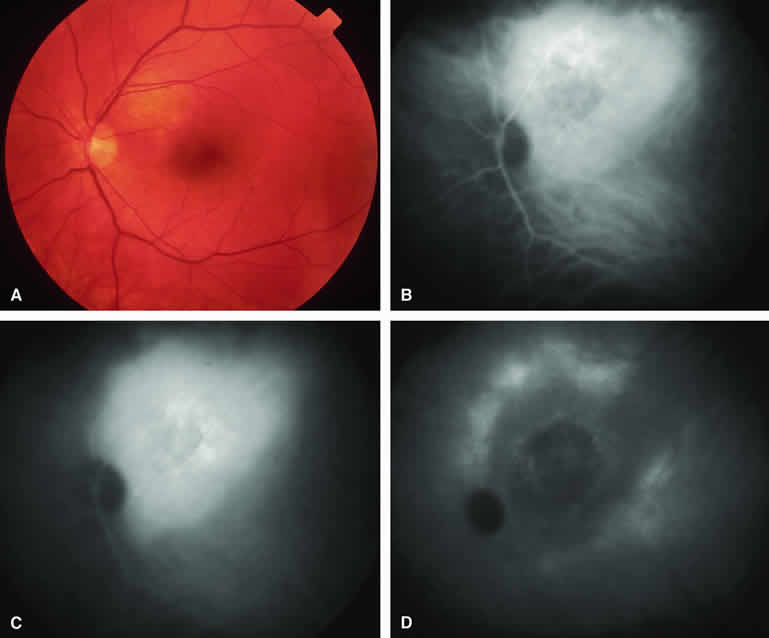

Typical Melanotic Choroidal Nevus

Fluorescein angiography of a typical choroidal nevus with bland surface features (see Fig. 1) shows the entire lesion to be hypofluorescent relative to the adjacent uninvolved choroid throughout the study. No large-caliber choroidal blood vessels are usually identifiable within the lesion. The retinal vasculature overlying the lesion appears well defined and normal on fluorescein angiography.